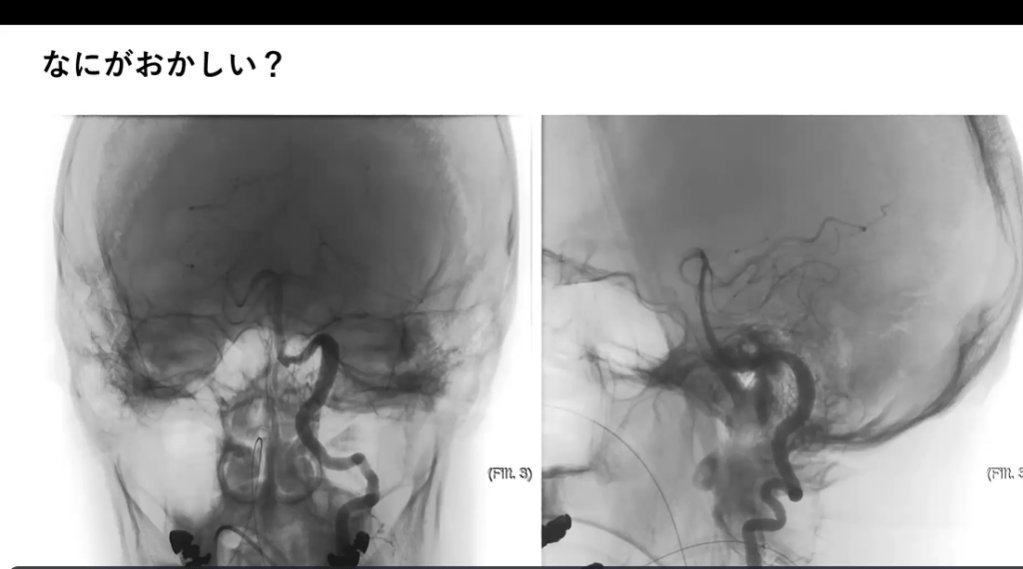

Azygos ACA, accessory MCA, anterior choroidal a.(時間配分的に問題なければ後頭蓋窩の血管も、後頭蓋窩の血管はある程度概論でも紹介する)(田上)